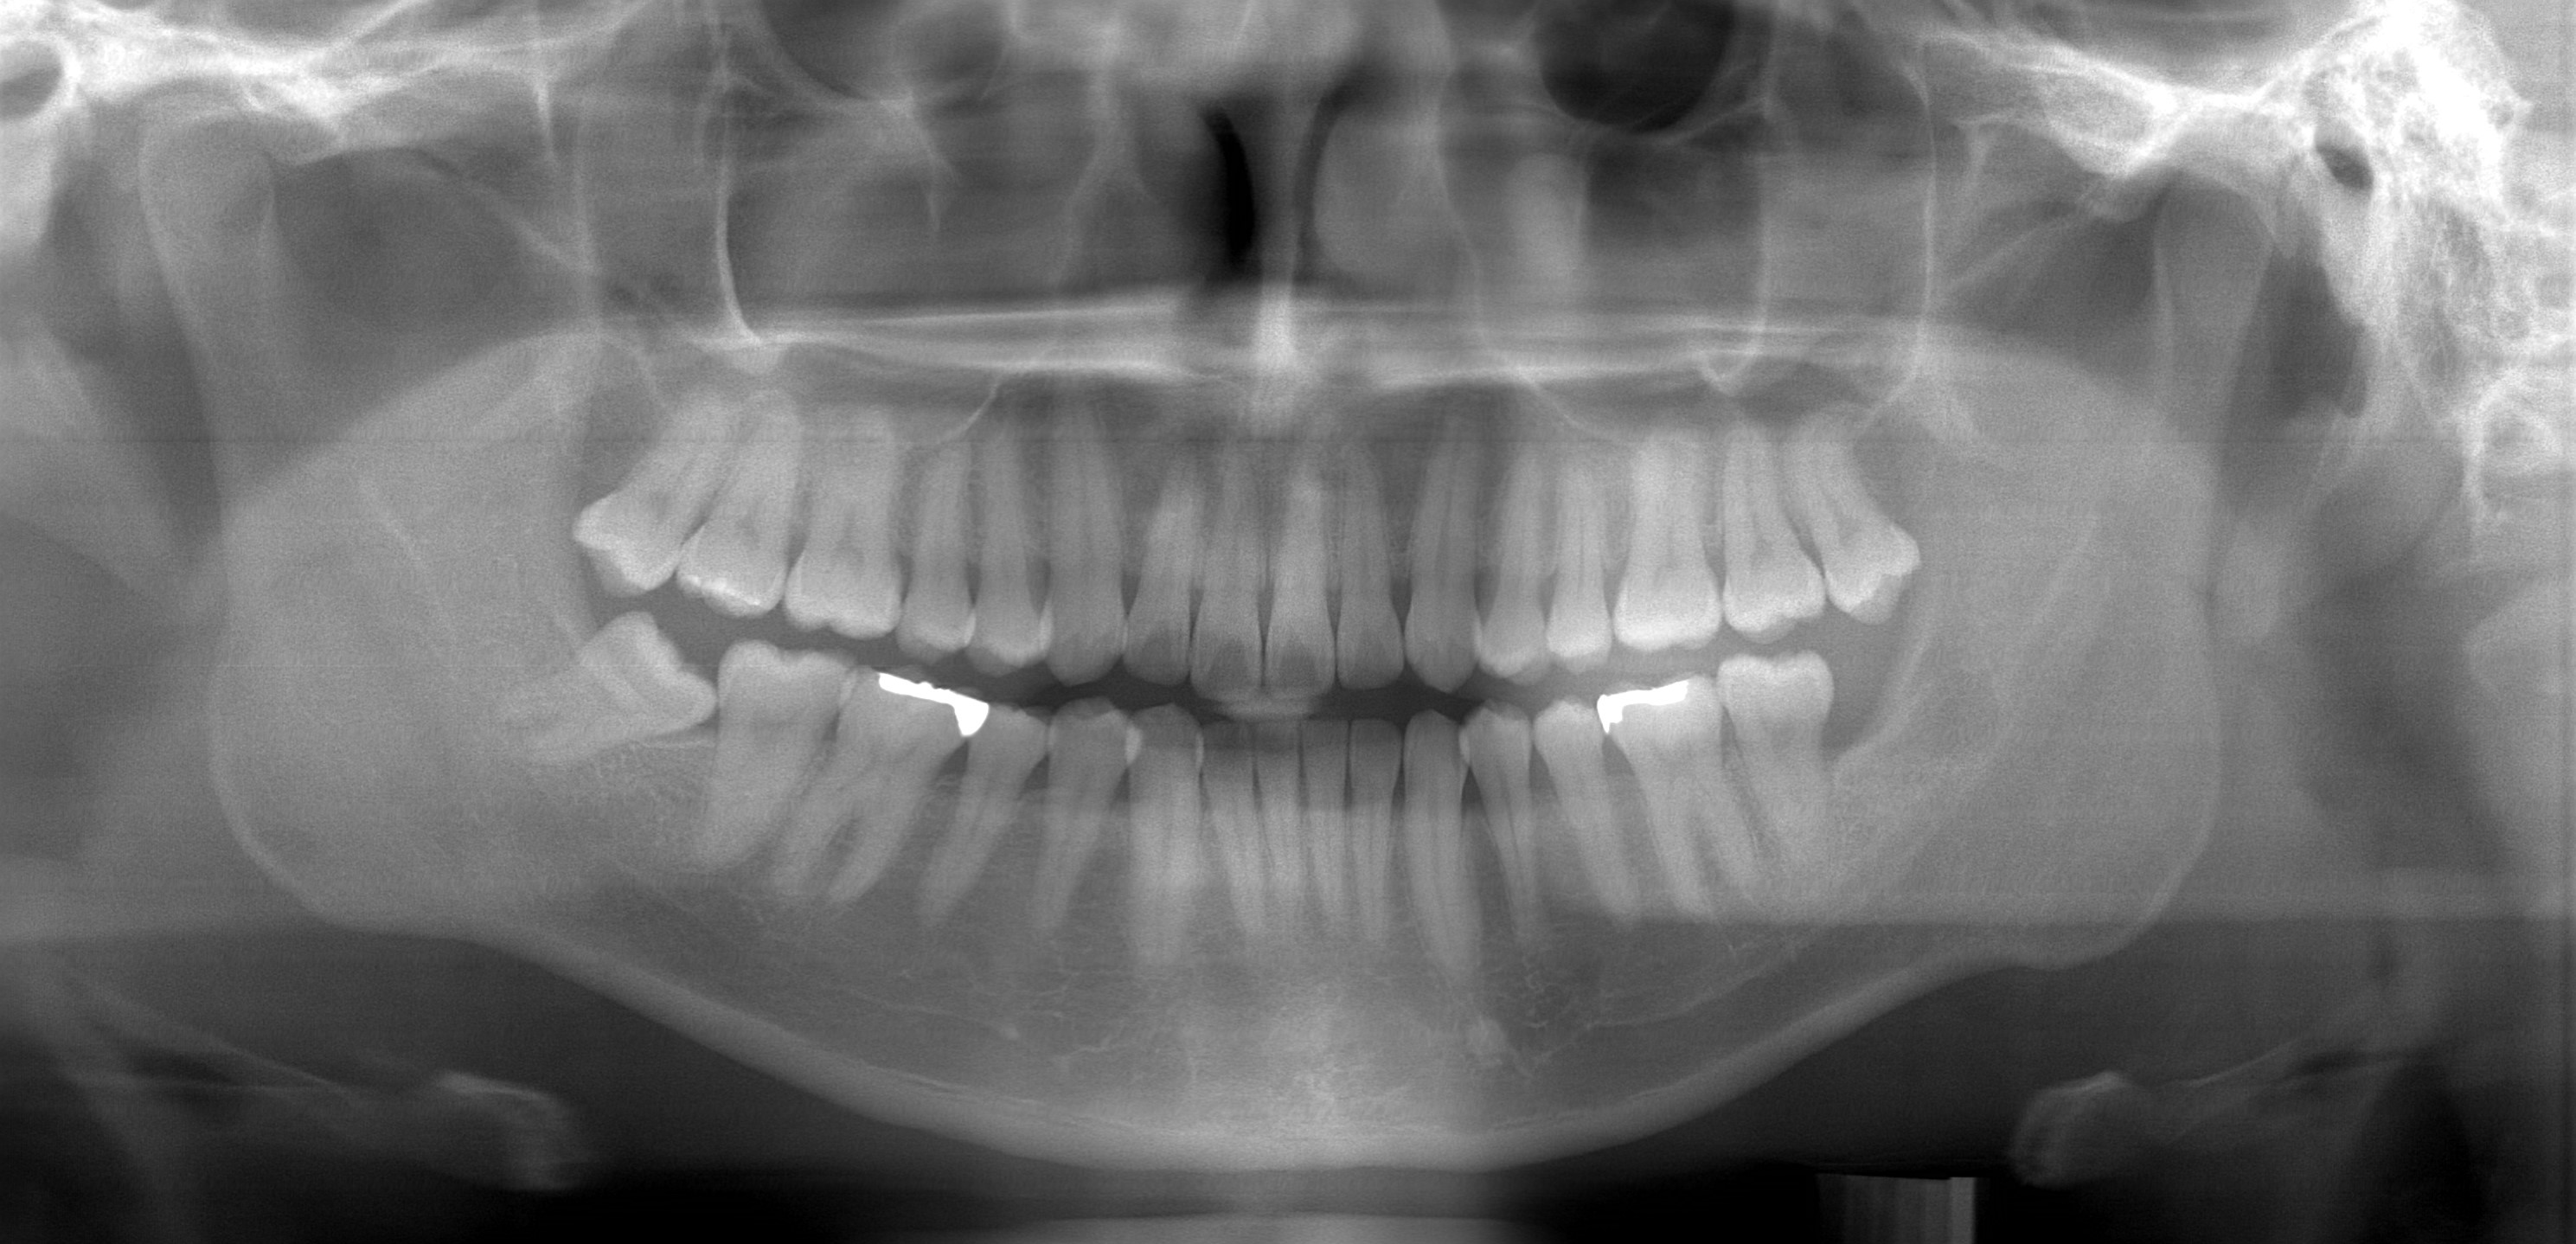

デジタル式パノラマ撮影

パノラマレントゲンは平面的な画像しか得られないため、一方向からしか疾患や症状を見られません。確認したい部分の大きさなどはある程度知ることはできますが、全体を大きく把握するために撮影なので詳しい情報が必要な場合は更に種類の異なるレントゲンを撮る必要があります。